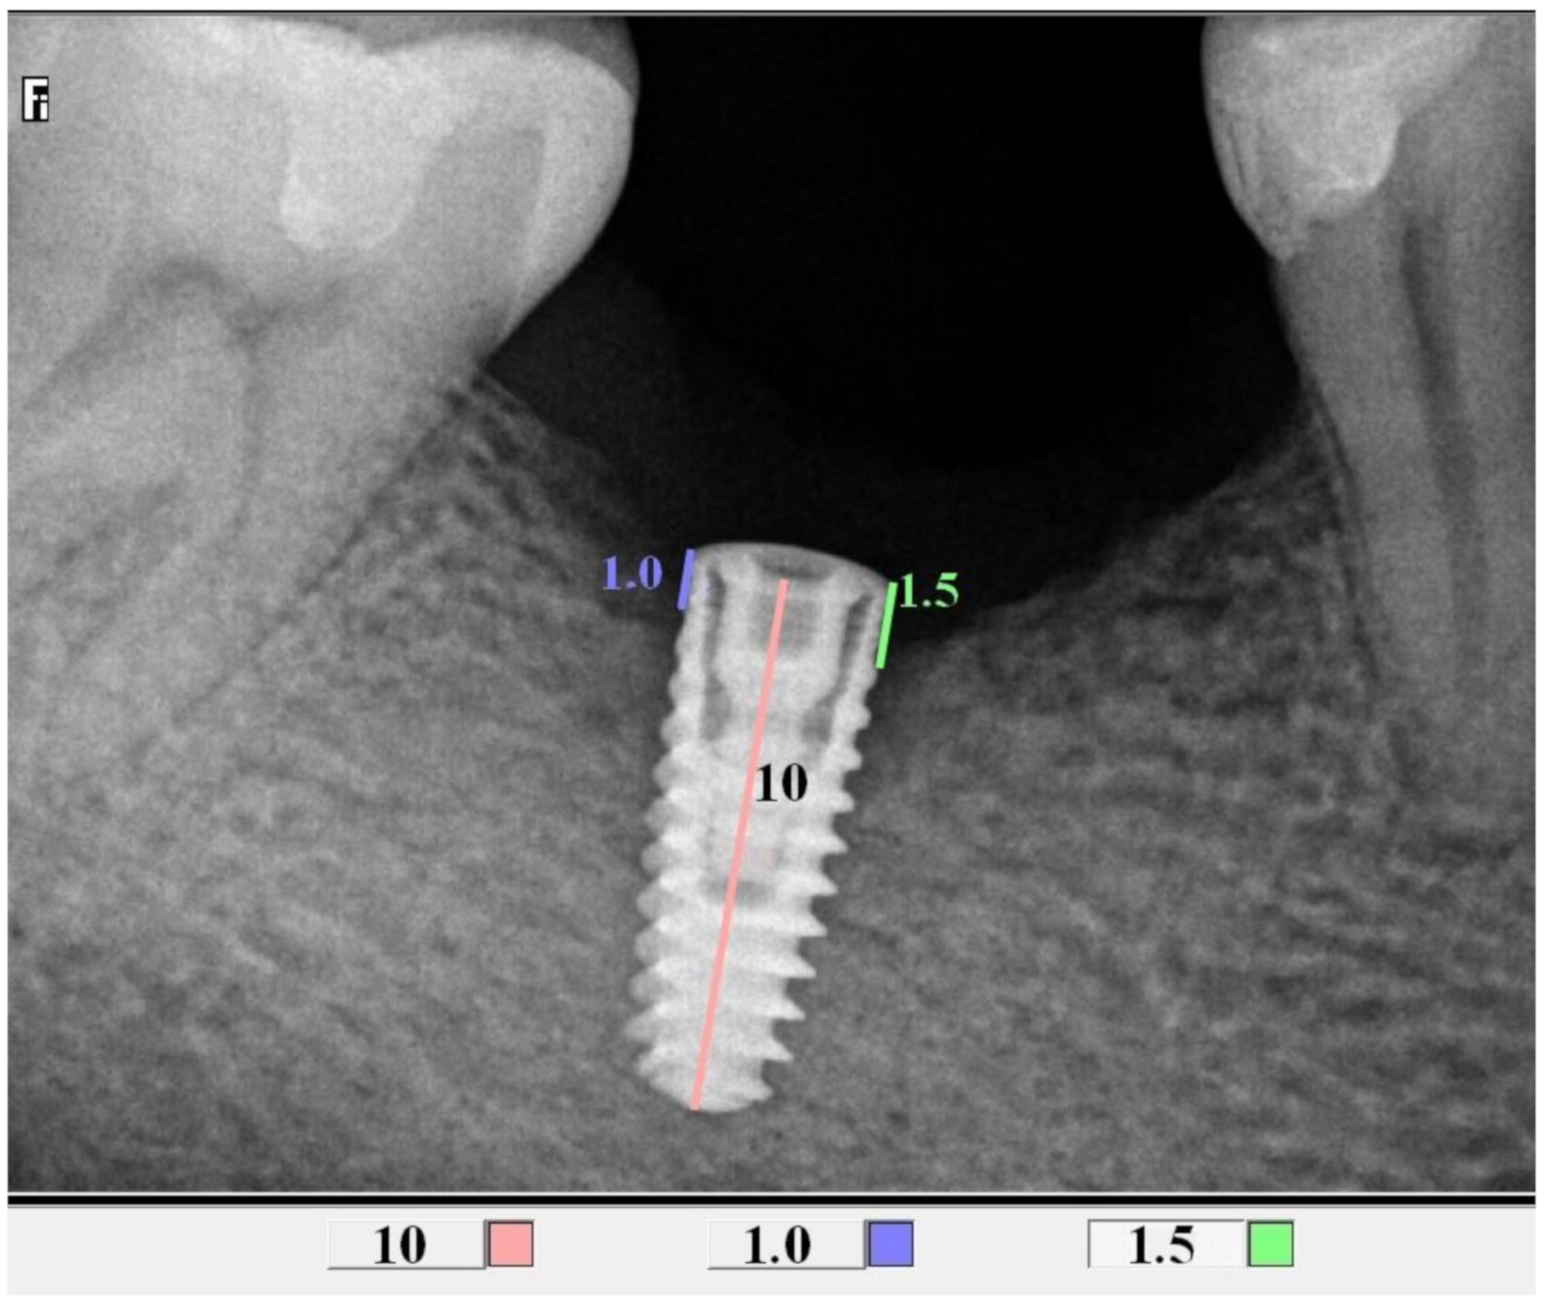

2.4. Radiological Assessment of the Bone Level in the Proximity of the Implant

| Implant lenth | 8 mm | 8 (18.60%) | 13 (27.08%) | 10 (32.26%) | 31 (25.41%) | 0.71 |

| 10 mm | 30 (69.77%) | 31 (64.58%) | 19 (61.29%) | 80 (65.57%) | F | |